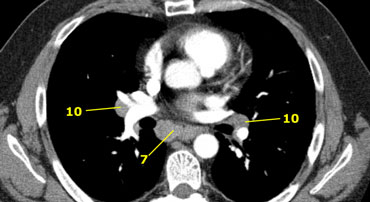

7. Subcarinal nodes

These nodes are located caudally to the carina of the trachea, but are not associated with the lower lobe bronchi or arteries within the lung.

On the right they extend caudally to the lower border of the bronchus intermedius.

On the left they extend caudally to the upper border of the lower lobe bronchus.

On the left a station 7 subcarinal node to the right of the esophagus.